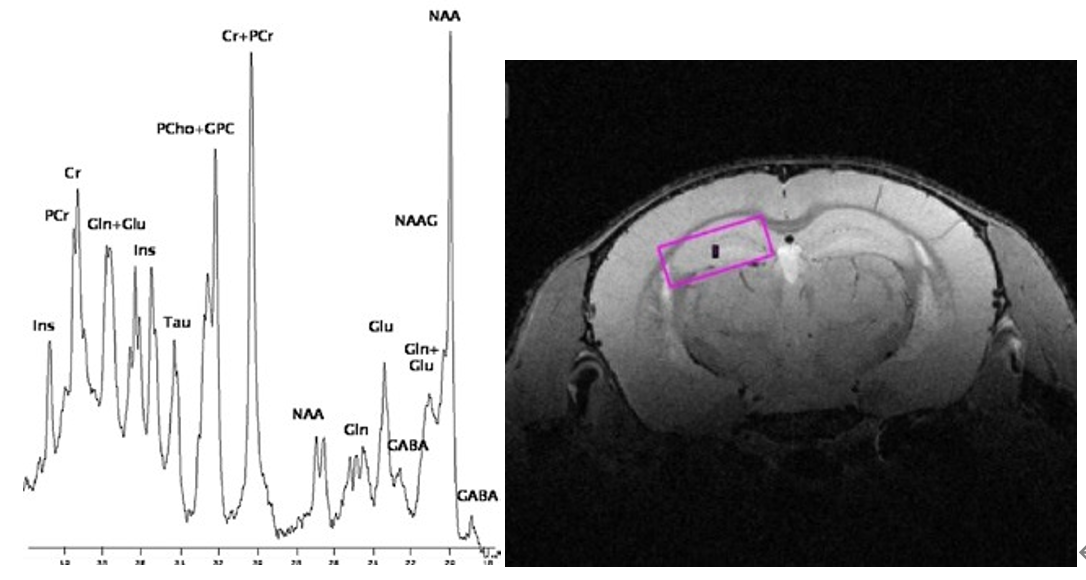

5、磁共振波譜

高強(qiáng)磁場下的磁共振波譜給研究腦部、腫瘤等代謝情況提供新的有效工具,布魯克卓越的活體定域譜技術(shù)實(shí)現(xiàn)小于10毫秒的回波時間,可以研究更廣泛的代謝物。精密的勻場算法減小譜峰的重疊,達(dá)到最好的波譜分辨力。

高強(qiáng)磁場下的磁共振波譜: